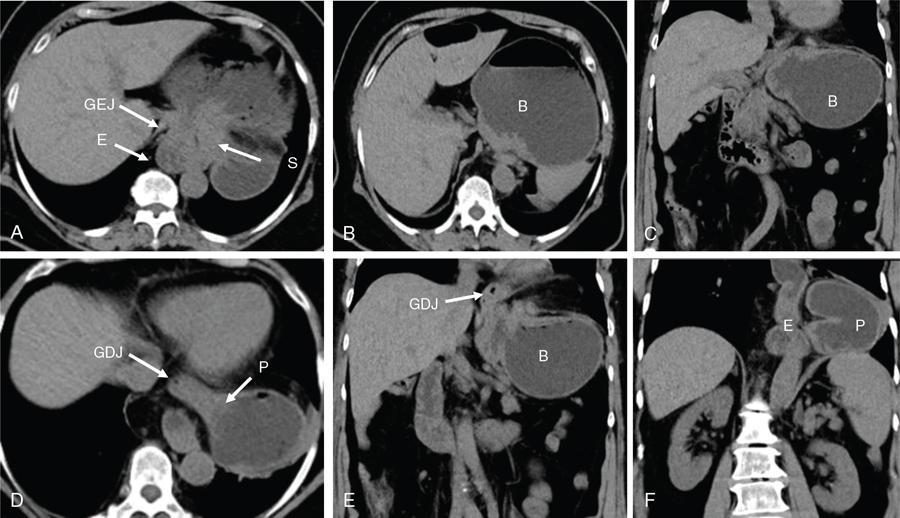

Swarup Nellore, Soumil Vyas, Ujwal Bhure, Ankit Jain, Richa Kothari, Daksh Mehta, Divya Kantesaria, Disha Lokhandwala, Karthik Ganesan The stomach is the most dilated portion of the gastrointestinal tract positioned between the oesophagus and the small intestine occupying the epigastrium, left hypochondrium and umbilical regions of the abdomen performing a multitude of functions including storage and mixing of food and controlling the passage of food into the intestine. Anatomically, the stomach is divided into the following parts (Fig. 8.2.1): the gastric cardia is the portion immediately adjoining the oesophageal opening into the stomach. The fundus is the dome-shaped part above the horizontal plane of the cardiac orifice which undergoes receptive relaxation and is the site of the autonomic pacemaker. The body is the largest part of the stomach extending from the cardiac orifice to the level of incisura angularis (notch like bend in the mid lesser curvature) containing majority of parietal cells (which secrete hydrochloric acid), chief cells (pepsinogen) and enterochromaffin-like cells (ECL). The pylorus is the tubular distal portion of the stomach which is further divided into the gastric antrum and pyloric canal. The pyloric antrum containing G-cells producing gastrin extends from the incisura angularis up to the pyloric sphincter which is an anatomical sphincter formed by concentric thickening of the circular muscle coat and encircles the narrow-slit like pyloric canal. The left dome of diaphragm and oesophagus lie superior to the stomach while the greater omentum and pancreas lie inferiorly. Spleen and liver lie on either side laterally while the transverse mesocolon is located inferolaterally. Diaphragm, greater omentum, left lobe of liver and anterior abdominal wall are anteriorly related to the stomach and contents of lesser sac including pancreas, spleen, splenic artery, transverse mesocolon, left kidney and adrenal gland lie posteriorly. The stomach is embryologically derived from the primitive foregut and is suspended anteriorly by the ventral mesogastrium and posteriorly by the dorsal mesogastrium. During development as the stomach rotates, the peritoneum grows and condenses to form perigastric ligaments, which contain blood vessels, lymphatics, lymph nodes, nerves and fat. The liver forms in the ventral mesogastrium, which develops into the falciform ligament, gastrohepatic ligament (GHL) and hepatoduodenal ligament (HDL). The spleen and pancreas form within the dorsal mesogastrium, which fuses with the posterior abdominal wall to form the gastrocolic ligament (GCL), gastrosplenic ligament (GSL) and splenorenal ligament (SRL). The perigastric ligaments are identified anatomically by the vessels contained in them (Fig. 8.2.2). The gastric cardia and lesser curvature of the stomach are attached to the inferior surface of liver by the lesser omentum by the gastrohepatic ligament respectively which contains the left and right gastric vessels. The inferior free edge of the gastrohepatic ligament extends inferiorly as the hepatoduodenal ligament between the porta hepatis and proximal duodenum gastrophrenic ligament extends between the stomach and the left hemidiaphragm. The gastrocolic ligament identified by the left and right gastroepiploic vessels, connects the greater curvature of the stomach to the anterior surface of the transverse colon. This ligament extends inferiorly as the greater omentum which is a double-layered peritoneum forming a drape anterior to the bowel loops. The gastrosplenic/lienogastric ligament bridges the posterolateral wall of the fundus and greater curvature along the proximal body of the stomach to the splenic hilum and contains the short gastric vessels. The gastrosplenic ligament is contiguous with the lienorenal ligament and both these structures constitute the lateral boundary of the lesser sac. Macroscopically the stomach shows a thick vascular mucosal lining in the form of longitudinal folds called gastric rugae. Microscopic layers of the stomach include mucosa, submucosa, muscularis externa and serosa. The mucosa includes surface mucus cells with simple columnar epithelium, gastric pits, gastric glands, lamina propria and muscularis mucosa. Submucosa includes connective tissue with submucosal Meissner’s plexus. Muscularis externa comprises three smooth muscle layers (longitudinal, circular and oblique) and Auerbach myenteric plexus. The outermost layer called serosa consists of loose connective tissue and visceral peritoneal lining. The arterial supply of stomach is constituted by the branches of celiac artery predominantly in the form of two anastomotic arcades along the lesser and greater curvature. Left gastric artery, a direct branch of the celiac trunk supplies the upper part of the lesser curvature while the lower part is supplied by the right gastric branch of the common hepatic artery arising at the upper border of pylorus. The left gastroepiploic artery, a branch of splenic artery, supplies the upper part of greater curvature and the inferior portion is supplied by the right gastroepiploic artery which is a branch of the gastroduodenal artery. The fundus additionally receives few small short gastric branches from the splenic artery. The veins follow the arteries in their nomenclature. Left and right gastric vein show direct drainage into the portal vein. The splenic vein derives flow from the short gastric and left gastroepiploic vein whereas the right gastroepiploic vein drains into the superior mesenteric vein. Pylorus can be surgically delineated by the prepyloric vein of Mayo lying on its anterior surface. Intrinsic nerve supply consists of the myenteric plexus of Auerbach and submucosal plexus of Meissner. Extrinsic nerve supply consists of sympathetic and parasympathetic components. Sympathetic nerve supply arises from T5 to T9 spinal cord segments supplying the celiac plexus via the greater splanchnic nerve. The plexuses then travel along the respective branches of celiac artery supplying the stomach. Parasympathetic nerve supply is derived from oesophageal plexus of vagus dividing into two vagal trunks. Right (posterior) vagus gives off the posterior gastric branch also called the criminal nerve of Grassi supplying the cardia and fundus of stomach. Right vagus then gives off a celiac branch and continues along lesser curvature of stomach as the posterior gastric nerve of Latarjet supplying the antrum, body and pylorus. Left (anterior) vagus gives off a hepatic branch then continues along the lesser curvature as the anterior nerve of Latarjet supplying the antrum, body and pylorus. Crow’s feet innervation to antropyloric area are important surgical landmarks preserved during highly selective vagotomy receiving branches from both major nerve trunks (anterior and posterior) at the incisura angularis. Anatomical lymphatic drainage is divided into three areas. Area I is the superior two-thirds of stomach draining via the nodes along left and right gastric vessels into the aortic nodes. Area II includes the right two-thirds of the inferior one-third which drains through the nodes along right gastroepiploic vessels via the subpyloric nodes into aortic nodes. Area III includes left one-third of greater curvature draining via short gastric and splenic nodes into suprapancreatic nodes and ultimately into aortic nodes. Gastric lymph node stations are divided into 4 levels with 16 lymph node stations: Paraesophageal nodes below the diaphragmatic hiatus (17) and above the diaphragmatic hiatus (18) are also included. The stomach first appears as a fusiform dilatation in the distal endodermal foregut in the 4th week of embryonic life. The dorsal and ventral mesogastrium suspend the developing stomach to the respective abdominal walls. Preferential growth along the dorsal border of the developing stomach leads to the formation of a convex dorsal border (greater curvature) and a concave ventral border (lesser curvature). The stomach subsequently undergoes a sequence of rotations. The first (90 degrees) clockwise rotation occurs around the longitudinal axis which brings the lesser curvature to the right and greater to the left. This rotation also brings the dorsal mesogastrium towards the left and ventral to the right creating a space behind the stomach called as the lesser sac or omental bursa. The second clockwise rotation occurs around the anteroposterior axis, with the caudal or pyloric part moving upwards and to the right while the cephalic or cardiac portion moves towards the left and slightly downward causing the stomach to assume its final anatomic position. This rotation causes the dorsal mesogastrium to bulge downwards and grow further to eventually become a double-layer apron called the greater omentum. The developing liver divides the ventral mesogastrium into the falciform ligament extending from the ventral abdominal wall to the liver with its lower free edge forming the ligamentum teres, the visceral peritoneum surrounding the liver and the lesser omentum with its two parts – the hepatogastric ligament and hepatoduodenal ligament. The dorsal mesogastrium gives rise to the redundant greater omentum, gastrocolic ligament, gastrosplenic ligament and lienorenal ligament. These perigastric ligaments help us in deciphering patterns of the spread of gastric malignancies and in taking decisions regarding their management and prognostication. These will be further explained in detail under the section of gastric malignancies. An abdominal radiograph is often the initial imaging test for evaluation of acute abdominal pain. The gastric bubble is seen below the left hemidiaphragm in situs solitus. Presence of gastric outlet obstruction may show a distended stomach with gasless small bowel. Hollow visceral perforation is diagnosed by free air seen under domes of diaphragm. Also, the presence and position of various tubes like the nasogastric tube can be confirmed using a radiograph. A fluoroscopic upper gastrointestinal (GI) examination is the radiological study of oesophagus, gastro-oesophageal junction, stomach, duodenum up to duodenojejunal junction by oral administration of contrast. Barium sulphate is a good contrast medium for GI studies as it is radio-opaque, non-absorbable, inert to tissues and can be used for double-contrast studies. Patient should be nil by mouth at least 4 hours prior to the examination. In a single contrast examination, the emphasis is on mucosal relief, luminal distention with contrast material and compression. In the erect position, a small amount of contrast is given to swallow while the oesophagus is visualized under fluoroscopy. The table is then made horizontal and the patient is rotated in a clockwise manner as seen from the foot end of the patient, thus ensuring good coating of the stomach mucosa. Mucosal relief images are then obtained in supine and prone positions to demonstrate the mucosal fold pattern and possible filling defects. After giving some more contrast, the patient is turned oblique with the right side dependent and spot images of the duodenal cap and C loop are taken both in distended and empty states. The patient is again positioned erect and more images of duodenal cap and loop are taken. Further contrast is given to optimally distend the lumen and assess for possible contour abnormalities, wall rigidity and strictures. Compression techniques help assess for filling defects and lesions, in the compressible areas of the stomach. Images are taken in multiple positions – supine, prone, right anterior oblique, right lateral, left posterior oblique in recumbent and right anterior oblique in erect position. Gastric peristalsis and emptying can be observed at fluoroscopy. Advantages of the single contrast technique are that it can be performed quickly, well-tolerated and requires less patient cooperation as compared to double-contrast studies. It can even be performed in physically debilitated patients. Barium is contraindicated in suspected cases of perforation, aspiration, fistula or recent GI biopsy. Single contrast examination can be performed using water-soluble iodinated contrast media in these cases and immediate postoperative patients. Earlier, ionic contrast like Gastrograffin was used. However, due to its high osmolarity, nowadays, non-ionic contrast is preferred as it causes less electrolyte imbalance due to its low osmolarity. Also, it delineates the GI tract very well due to less dilution. Double-contrast studies provide better evaluation of the mucosa than do single-contrast studies. Here, the emphasis is on coating the mucosa with barium and distending the lumen with gas. A well-performed double-contrast study is biphasic and also incorporates some single-contrast techniques. The initial part of the examination is the same as a single contrast examination to obtain the mucosal relief images. Then, gas-forming powder that produces carbon dioxide within the stomach lumen is given with more barium. With the double-contrast technique, the mucosa is coated with a high-density barium suspension and the lumen distended with gas. The patient is rotated in a clockwise manner as seen from the foot end of the patient, thus ensuring good coating of the stomach mucosa. Spot images of the distended stomach are taken followed by the duodenal cap and loop in oblique right-side dependent position. Patient is brought back to erect position erect and more images of stomach, duodenal cap and loop are taken. Further contrast is given to distend the lumen. Residual fluid or food debris in the stomach impairs stomach coating, and lack of adequate coating may preclude visualization of lesions. In addition, optimal gaseous distention is important as underdistention will cause a false appearance of abnormally thickened, and overdistention can obliterate abnormal folds. With normal gastric anatomy, the gastric fundus is best visualized in the upright left-posterior-oblique position, the body in the supine anteroposterior position and the antral-pyloric region in the supine left-posterior-oblique position. The normal gastric mucosal surface should be smooth on double-contrast studies. Areae gastricae appear as reticular networks of polygonal tufts which, owing to the presence of barium in the narrow intervening grooves, are coated with white lines. These are seen most often in the antrum or body of the stomach but can also be seen in the fundus. Areae gastricae are identified on double-contrast studies in 70% of patients and are seen more often in elderly patients. Polygonal tufts should normally range in size from 2 to 3 mm in the antrum and 3 to 5 mm in the body and fundus. Normal gastric folds are more prominent in the proximal to mid stomach and more undulating along the greater curvature as compared with the lesser curvature. Antral folds should be typically effaced with the double-contrast technique. Gastric cardia is characterized by three or four stellate folds radiating from a central point at the gastro-oesophageal junction; this is known as the cardiac rosette and is best visualized in the supine right-lateral position. Ultrasonography (USG) is the modality of choice to visualize hypertrophic pyloric stenosis in infants. Although USG does not play much of a role in adults for imaging of stomach due to reflection of sound waves by air, luminal distension with water may enable to identify mucosal – submucosal pathologies and to assess perigastric relationships in pathologies. CT can not only evaluate the location and anatomy of the stomach, but also provide additional information about the relationship of the stomach to surrounding structures. An optimal CT examination of the stomach includes good stomach distension with a well-visualized wall. Gastric distention can be achieved by the oral administration of negative or positive luminal contrast. Positive contrast agents include a 1%–2% barium suspension or a 2%–3% solution of a water-soluble iodinated contrast agent. Water-soluble agents should be used in cases of suspected perforation. Positive agents provide a bright lumen with better identification of luminal encroachment or diverticula but may limit detailed evaluation of gastric wall enhancement. Positive contrast also may not mix well with gastric contents, producing a pseudotumor appearance. On the other hand, neutral or negative contrasts agents, usually water, produce a low attenuation lumen which allows for more detailed evaluation of the gastric wall and its enhancement pattern following intravenous contrast and is preferred for three-dimensional imaging. Multidetector CT with thin collimation allows for postprocessing in any orthogonal plane. The CT data of the stomach can be manipulated to simulate endoscopic images (virtual gastroscopy). This display technique accentuates the stomach wall and folds. Prior to evaluating the stomach with CT, oral contrast is administered at repeated intervals as well as immediately prior to scanning. Multiphasic scanning after intravenous contrast may be employed at 25–35 seconds (late arterial), 55–75 seconds (venous phase) after contrast injection. Normally, the gastric wall may enhance to approximately 120 Hounsfield Units after intravenous contrast administration. The mucosa may enhance more than the relatively lower-attenuation muscularis propria. Abnormal enhancement of the wall can highlight pathologic processes. The CT appearance of the stomach also depends upon the degree of distention. When well distended, the body and fundus is less than 5 mm thick, though the normal antrum may appear slightly thicker. The presence and pattern of wall enhancement, degree and location of wall thickening, and length of an involved segment may be assessed. Comprehensive MRI examination of the stomach and duodenum by the combined use of T2-weighted single-shot and T1-weighted gradient echo (GRE) – with and without fat suppression, and gadolinium-enhanced 3D GRE helps to detect the spectrum of gastric diseases on MRI. These sequences minimize artefacts from bowel peristalsis, increase the sensitivity of detection of peritoneal and serosal disease by suppressing the high signal of intra-abdominal fat, widen the dynamic range of abdominal tissue signal intensities and distinguish between intraluminal bowel contents and bowel wall. The gastric rugae are well seen on T2-weighted single-shot spin-echo images and their enhancement appears as bands of enhancing tissue arranged perpendicular to the external contour of the gastric wall. The normal gastric wall enhances more intensely than other segments of bowel on immediate postgadolinium SGE images. Water is frequently used as an oral contrast agent when imaging the upper GI segment-stomach and duodenum. Noninvasive dynamic study for assessment of gastric motor function and wall motility can also be done using MRI for diagnosis of gastroparesis. Gastric emptying scintigraphy (GES) is a well-established radionuclide procedure to evaluate patients with suspected gastric motility disorder, more so for non-invasive assessment of gastroparesis in patients with symptoms of postprandial fullness, nausea, vomiting, abdominal pain, bloating, early satiety, loss of appetite, as well as weight loss. Gastroparesis, commonly seen in diabetics, is a condition that affects the normal spontaneous movement of the gastric muscles, leading to impairment of gastric motility, because of which the stomach cannot empty itself of food in a normal fashion and time. GES can also provide useful information with regards to assessment of impaired gastric motility in patients with GERD (gastro-oesophageal reflux disease) unresponsive to routine therapy, diabetics with poor glycemic control, and also in patients with colonic inertia who are being considered for colectomy (since benefits of colectomy are mitigated in patients with concurrent impaired gastric emptying). On the other hand, GES is also useful for assessment of rapid gastric emptying (GE), which is a major factor in dumping syndrome, often seen post peptic ulcer surgery, with or without vagotomy. The solid or liquid component of a meal is radiolabelled with a radiopharmaceutical, which is consumed by the patient and subsequently measured gastric radioactive counts by scintigraphy correlate with the volume of the meal remaining in the stomach. Solid-phase GES is used for the evaluation of gastric motility disorder/gastroparesis. Liquid-phase gastric emptying is generally not clinically useful since it is often in the normal range in spite of deranged emptying for solids even with severe gastroparesis. The preferred radionuclide meal for the gastric emptying scintigraphy includes egg-white radiolabelled with 0.5–1.0 mCi of Technetium-99m (99mTc) [approximate caloric value of 255 kcal]. Two large eggs (egg-whites), two slices of bread, fruit jam, water (120 mL approximately), and the radiopharmaceutical (0.5–1.0 mCi of 99mTc–sulphur colloid). For patients allergic, to eggs, alternative meals like oatmeal or Liquid Ensure nutrient supplement can be used. Reporting should include the percentage of radiotracer retained in the stomach at defined time intervals. The normal reference values for comparison are as follows: Grading the severity of the delay in gastric emptying based on gastric retention at 4 hours of the study: Gastro-oesophageal reflux (GER) is a common condition in infants and children, wherein there is reflux of stomach contents into the oesophagus, due to possible incompetence of gastro-oesophageal sphincter, which can lead to development of symptoms like regurgitation, heartburn, cough and dyspepsia. Children can present with recurrent respiratory infections, iron deficiency anaemia and failure to thrive. It is often a self-limited process in infants and children which usually resolves by 12–18 months of age. On the other hand, gastro-oesophageal reflux disease (GERD) is a chronic pathological process which can be troublesome. Scintigraphic evaluation of gastro-oesophageal reflux, popularly known as ‘milk scan’, is an established imaging modality and has sensitivity of 75%–100%. This radionuclide test for gastro-oesophageal reflux is physiological and quantitative and commonly used for diagnosis in neonates and infants. Four hours fasting is preferred. A liquid meal consisting of formula, milk, or orange juice mixed with the radiopharmaceutical is administered either orally or by nasogastric tube. 99mTc–sulphur colloid. Dose: 0.2 to 1 mCi. After administering the liquid meal and allowing burping, the baby is positioned supine under the gamma camera detector head, including chest and upper abdomen in the field of view. A radioactive marker can be placed at the mouth. Anterior serial dynamic planar images are acquired for around 60 minutes with a framing rate of 5–10 seconds per frame. Delayed anterior static image of the chest may be acquired additionally. The acquired frames are reviewed in cinematic display for visual estimation and to look for reflux of the radiotracer into the oesophagus. Reflux is seen as distinct spikes of radiotracer activity into the oesophagus. For quantitative estimation, the volume of each episode of reflux, frequency of episodes and rate of reflux clearance from the oesophagus are taken into consideration. Percentage of reflux is calculated by drawing an ROI over the oesophageal spike of radiotracer activity and the counts are calculated and expressed as a fraction of the gastric activity counts. Values greater than 5% are suggestive of reflux. Semiquantitative evaluation grades each reflux event: Based on this, four categories can be formulated: The greater the number of high-level reflux events and the longer they last, more severe is the gravity of the problem. Pulmonary aspiration should also be looked for, though the sensitivity of detection is poor. Liquid gastric emptying can be evaluated during the same study up to 2 hours. Normal values for liquid gastric emptying are: Endoscopy is the preferred examination to evaluate for majority of the upper GI symptoms. It is very sensitive in detecting mucosal lesions and simultaneously, biopsies can be taken. In cases of upper GI bleed, endoscopy can not only detect the site and cause of the bleed, but also further treatment like adrenaline/sclerosant injection or ligation can be done. EUS can provide detailed assessment of the 5 layers of the gastric wall and is thought to be the most accurate non-surgical method for local tumour staging (Fig. 8.2.9). For subepithelial (submucosal) gastric lesions, EUS can assess the echogenicity of a lesion, the exact layer of the gastric wall which is involved (accurate T-staging of a tumour) and assess for the presence of blood flow with Doppler ultrasound to help ascertain the likely aetiology. EUS-guided fine needle aspiration may also provide additional diagnostic information. Hiatus hernia is a common positional abnormality of stomach, characterized by herniation of abdominal contents, commonly the gastro-oesophageal junction and stomach, into the mediastinum above the diaphragm through a widened oesophageal hiatus. The oesophageal hiatus is an elliptical opening with complex anatomy formed by the right and left crus of the diaphragm. However, the most common anatomical description is of the right crus splitting into two bundles, the right and left, which form a sling encircling the distal oesophagus and may be reinforced by the left diaphragmatic crus. The distal oesophagus is typically anchored to the oesophageal hiatus by a main restraining structure which is the phrenicoesophageal ligament/membrane (the fascia of Laimer) which is a condensation of endo-thoracic and endo-abdominal fascia and this membrane circumferentially inserts into the oesophageal musculature in close proximity to the squamocolumnar junction (SCJ). The ligament maintains the competence of the oesophageal hiatus and prevents rostral herniation of the gastro-oesophageal junction and stomach. During normal physiological swallowing, the longitudinal layer of the oesophageal muscularis propria contracts with associated oesophageal shortening and stretching of the phrenicoesophageal ligament/membrane resulting in the transient elevation of the oesophagogastric junction and portion of the stomach above the hiatus. At the end of the swallowing mechanism, the elastic recoiling of the phrenicoesophageal ligament/membrane restores the migrated segment to its normal position. With ageing-related wear and tear, the ligament becomes lax with progressive depletion of elastin fibres resulting in proximal migration of the gastro-oesophageal junction and stomach. Other potential risk factors of fibromuscular degeneration are caused by increase in the intra-abdominal pressure as occurs in obesity and pregnancy. The majority of the symptomatic cases of hiatal hernia present with the clinical symptoms of gastro-oesophageal reflux disease (GERD) with most characteristic manifestations of acid regurgitation, heartburn, dysphagia, epigastric or chest pain and even chronic iron deficiency anaemia. Large hernias may also present with early satiety. Conventionally, hiatus hernias are classified into sliding and paraesophageal varieties. The current comprehensive anatomic classification has evolved to include a categorization of hiatal hernias into Types I–IV and is necessary especially regarding the treatment approach, as indications for the surgical method are quite different between sliding and paraesophageal hernias. Majority of hiatus hernias (95%) are sliding hiatus hernias (type I), the remaining type II–IV hernias as a group are referred to as paraesophageal hernias (PEH), with more than 90% of these comprising type III, and the least common being of type II. The assessment of hiatus hernia can be done by various modalities including radiological, manometry and endoscopy studies. The diagnosis of a large hiatus hernia is straightforward, however, identifying a small one is challenging due to mobility of the gastro-oesophageal junction during physiological process like deglutition and respiration. According to the SAGES Guidelines, only those investigations which will alter the clinical management of the patient should be performed. Radiological investigations are usually indicated for diagnosis and presurgical evaluation. Plain chest radiographs demonstrate opacity within the chest typically in the midline overlapping the cardiac shadow or paramedian location (Fig. 8.2.14A), with or without an air-fluid level. Barium swallow radiography is still considered an easy tool for diagnosis of hiatus hernia and provides essential information about the size, location, motility dysfunction, stricture secondary to GERD and stenosis. The evaluation of hiatus hernia requires understanding of anatomical radiographic landmarks like phrenic ampulla, A ring and B ring (or Schatzki’s ring) on a barium study (Fig. 8.2.14B). The phrenic ampulla is a globular structure seen above the diaphragm and below the tubular oesophagus during a contrast swallow. The A ring represents a muscular ring visible at the upper margin of the phrenic ampulla and physiologically corresponds to the highest-pressure zone within the lower oesophageal sphincter, this is often seen as a transient indentation on the oesophageal lumen. The B ring identified in about 15% of individuals, representing the mucosal ring corresponds to the squamocolumnar junction (Z line) and divides the phrenic ampulla into the oesophageal vestibule (A ring to B ring) and the sliding hiatus hernia (B ring to the stomach below the diaphragm). The B ring is a persistent constriction which is not usually not more than 2–3 mm and despite mucosal, can sometimes be symptomatic and require dilatation. By convention, there must be a distance of 2 cm or more between the B ring and the hiatus, to call it a hiatus hernia as physiological migration up to 2 cm is known in normal individuals. Although not reliable, barium studies may also provide information about a short oesophagus, which is identified as a tubular straightened oesophagus with the oesophagogastric junction fixed far above the diaphragm and may be stenotic, the intrathoracic herniated stomach revealing a more elongated funnel/bell – shaped configuration. Cine fluoroscopy provides further additional information about the bolus transit through gastro-oesophageal junction. The major drawbacks of the procedure are non-visualization of B-ring in majority of the cases, radiation exposure, barium/iodine hypersensitivity, contraindication in pregnancy and increase risk of aspiration in paraesophageal hernia causing pneumonitis. Computed tomography (CT) scan is not routinely advised for the primary diagnosis of hiatus hernia but is indicated in cases of suspected complications like volvulus in paraesophageal hernia, obstruction, perforation and strangulation. Multi-slice CT with reconstruction in sagittal, coronal planes and 3D reformations have increased the sensitivity of CT in detection of hiatal hernia. Oesophagogastroduodenoscopy gives added advantage of real-time visual assessment of the mucosa of the oesophagus, stomach and duodenum. The common diagnostic criteria in endoscopic is proximal migration of gastro-oesophageal junction by >2 cm. Endoscopy can also determine the presence of erosive esophagitis or Barrett’s oesophagus. Further, the inability or difficulty of negotiating the scope into duodenum in the presence of a large hiatal hernia is diagnostic of paraesophageal hernia with volvulus. Evaluation of gastric viability is also important in patients undergoing emergency surgery for incarcerated hernias. The disadvantage of the procedure is lack of reproducibility; retching or belching of the patients during examination which can alter the location and anatomy of GEJ and excess air insufflation of the stomach which may exaggerate the size of the hernia. Oesophageal manometry is measured at the level of the diaphragmatic crura, however, manometric landmarks differ from that of barium study and endoscopy, and identified by pressure inversion point. In patients with a paraesophageal hiatal hernia, placement of the manometry catheter across the lower oesophageal sphincter and below the diaphragm can be difficult. The procedure is planned before surgery to exclude motility disorders like achalasia and to verify the integrity of oesophageal peristalsis. pH testing is not essential in the diagnosis of a hiatal hernia, but is necessary for a quantitative analysis of reflux in a case of hernia which can be relieved by antireflux surgery. Confirmation of abnormal gastro-oesophageal reflux on upper endoscopy, or increased oesophageal acid exposure on pH monitoring is necessary prior to operative intervention in patients with a sliding hiatal hernia. Nuclear medicine studies, transoesophageal echocardiogram (TEE) and endoscopic ultrasound (EUS) can also demonstrate hiatal hernias but are not routinely used for diagnosis. The main aim of treatment in symptomatic patient is to reduce the acid reflux. Lifestyle modifications are the first line of management and include weight loss, elevating the head of the bed preferably by 8 inches during sleep, avoidance of meals for atleast 2–3 hours before bedtime and elimination of ‘trigger’ foods. According to the SAGES Guidelines updated in April 2013, the treatment protocols are provided on the basis of types of the hiatus hernia. Type I (sliding) hiatus hernia are usually managed with proton pump inhibitors for 8 weeks, once or twice daily depending on the symptoms. Other alternatives are H2 receptor antagonists and antacids. If the patient is not relieved symptomatically by medication, surgical repair like laparoscopic fundoplication (Nissen or Toupet) can be done. Steps of fundoplication comprise surgically relocating the gastro-oesophageal junction below the diaphragm, maintaining an oesophagogastric angle to prevent gastro-oesophageal reflux, constructing a gastric wrap around the distal oesophagus to support the distal oesophageal sphincter and increase its resting pressure, and finally approximate the diaphragmatic hernia to narrow the widened hiatus. In all symptomatic Type II, III and IV hiatus hernia, surgical repair is strongly recommended as the primary treatment, particularly those with acute obstructive symptoms or which have undergone volvulus. Routine elective repair of completely asymptomatic paraesophageal hernias may not always be indicated and determinants for surgery should include the patient’s age and co-morbidities. These fundoplication surgeries are described later in the text. Gastric volvulus is an uncommon entity and characterized by abnormal rotation of the stomach (usually >180°) along the long or short axis, leading to variable degree of gastric obstruction, which can be of a closed-loop type resulting in strangulation. The exact incidence of gastric volvulus is unclear as patients with a chronic presentation may never be diagnosed.2 Approximately, 10%–20% cases of gastric volvulus occur in children less than 1 year, while the other 80% cases are detected in adults, of which 80%–90% are often encountered in the fifth decade of life.3 No significant predilection is seen with either sex or races. Gastric volvulus can be classified on the basis of aetiology, axis of rotation and duration of onset. While classification based on axis of rotation by Singleton is widely accepted and more relevant to the radiologist, classification based on duration of onset of symptoms is more relevant in clinical assessment. On the basis of axis of rotation (Fig. 8.2.15), gastric volvulus is divided into organoaxial volvulus, mesenteroaxial volvulus and the rarest combined/mixed type. Organo-axial volvulus, by far, the most common type of gastric volvulus, encountered often in the elderly, is characterized by rotation of the stomach along its long axis, that is, cardio-pyloric axis, and resulting in an ‘inverted stomach’ with a horizontal orientation, in the form of anterosuperior displacement of the antrum and posteroinferior rotation of the fundus, so that the greater curvature is displaced superiorly and lesser curvature caudally in the abdomen (Fig. 8.2.16). The site of obstruction in this type of volvulus is at the cardia or at pylorus. It has a higher predisposition towards strangulation and ischaemia. Organo-axial volvulus also shows association with the paraoesophageal hernia or diaphragmatic defects, which allows abnormal movement of the stomach along the long axis. If the degree of rotation is less than 180 degrees, the patient may have an incomplete or partial volvulus which is not completely obstructing and may be asymptomatic; it may be more appropriate to describe it as organo-axial position rather than volvulus. Mesenteroaxial volvulus is less commonly encountered (30%) and accounts for about 29% of cases, is reported more often in young adults or children. It occurs when the stomach rotates around its short (transverse) axis, that is, line connecting the midpoint between the lesser curvature and the greater curvature of the stomach, leading to a vertically oriented stomach, with anterior rotation of the pylorus, antrum and resultant displacement of the antrum above the gastro-oesophageal junction (Figs 8.2.17 and 8.2.18). The site of obstruction is usually at antropyloric region. It is usually not associated with a diaphragmatic defect and is often idiopathic. The third and rarest type of gastric volvulus is the combined type when the stomach shows both rotation along the short and long axes. Based on aetiology of rotation, gastric volvulus can be subdivided into either primary or secondary. Primary gastric volvulus representing 25%–30% of the cases, is more common in the adults. It occurs in the subdiaphragmatic location due to abnormality in the gastric fixation, exclusively because of disruption, laxity or absence of the gastric ligaments which anchor the stomach in place. These ligaments namely the gastrohepatic, gastrocolic, gastrophrenic, gastrosplenic and gastropancreatic ligaments, along with gastro-oesophageal junction and pylorus, provide anchorage and fix the stomach in place intra-abdominally, and prevent abnormal rotation of the mesentery. The primary gastric volvulus usually presents with the mesenteroaxial type of anatomical configuration. Around 70% of patients present with secondary gastric volvulus occurring due to abnormal rotation around the lead point formed by associated disease. The most common association of gastric volvulus is seen with paraoesophageal hiatus hernia. Other causative factors of volvulus include congenital or traumatic diaphragmatic hernia, diaphragmatic paralysis, eventration, connective tissue disorders, previous surgery, adhesions, peptic ulcer, neoplasm, splenomegaly or absence of the spleen and colonic overdistension. On basis of clinical presentation and speed of onset, gastric volvulus can be acute, subacute or chronic. Acute gastric volvulus is a surgical emergency and usually presents with sudden onset epigastric pain, distension, non-bilious vomiting or severe retching, depending on the degree of obstruction. The Borchardt triad of acute volvulus comprises severe epigastric pain and distention, retching but inability to vomit, and difficulty or impossibility of passing a nasogastric tube and may be observed in 70% of cases. Other symptoms include hematemesis due to mucosal sloughing in stomach gangrene or mucosal tear due to retching, dysphagia and dyspnea. Even after prompt treatment, mortality of acute gastric volvulus can be up to 30%–50%, likely secondary to gastric ischaemia, perforation or necrosis resulting from severe gastric obstruction (closed-loop obstruction) causing vascular compromise, making it a life-threatening surgical emergency. Chronic gastric volvulus represents spectrum of diseases from long-standing partially obstructed volvulized stomach with incomplete gastric obstruction on the one side, and intermittent volvulus of stomach with recurrent episode of acute symptoms as the other presentation. Chronic gastric volvulus usually presents with intermittent complaints of vague epigastric pain, non-bilious vomiting, dysphagia or early satiety, dyspepsia and sometimes regurgitation. Due to nonspecific clinical symptoms, diagnosing gastric volvulus is very challenging on the first instance and requires a high clinical suspicion. Diagnostic imaging, along with clinical findings are usually required to achieve the correct diagnosis, and also plays major role in excluding the other common differential diagnosis, like pancreatitis, cholecystitis or pneumonitis etc. The diagnostic modalities useful in suspected cases of gastric volvulus are plain radiographs, upper gastrointestinal contrast (barium) studies, computed tomography and upper gastrointestinal endoscopy. Plain chest and abdominal radiographs may reveal a radiolucent hollow viscus, with or without an air-fluid level, in the chest (when associated with PEH) or upper abdomen. The presence of a nasogastric tube may assist in identifying a malpositioned stomach, and administration of contrast via the nasogastric tube may be confirmatory in this regard. Furthermore, chest radiographs may identify evidence of underlying anatomic abnormalities predisposing to gastric volvulus, including elevated hemidiaphragm due to phrenic nerve palsy or diaphragmatic eventration and rib fractures suggesting prior thoracoabdominal blunt trauma. The plain radiographs may show two air-fluid levels in the antrum and fundus, or a single air bubble with no additional luminal gas in the supine position. A retrocardiac air-fluid level may be seen secondary to hernia and presence of intramural air (gastric emphysema) can be visualized as a radiolucent stripe in the gastric wall. At times a large hiatus hernia may be complicated by volvulus (Fig. 8.2.19). Passage of orally administered contrast like barium can demonstrate the anatomy and also assess the degree of obstruction. As mentioned above, the position of the gastric curvatures and the gastro-oesophageal junction are useful in differentiating the anatomical subtype of volvulus. Computed tomography may be more feasible in an acute emergency setting in order to identify abnormal gastric position, axis and multiplanar reconstructions, especially in the coronal plane, can well elucidate the findings and an associated complication like ischaemia. CT has an overall 90% accuracy in the diagnosis with identification of gastro-oesophageal junction and pylorus lying in close proximity to each other and the transition point at the pylorus known to have 100% sensitivity and specificity. Abnormal antral folds may be seen secondary to the twisting. Stenosis at the neck of the hernia is the CT finding with the second-highest sensitivity (77%–80%) and specificity (94%–97%). CT findings of oedematous or hypoenhancing gastric wall, pneumatosis, pleural effusion or pneumoperitoneum, as indicators of gastric ischaemia are not common but specific when identified. An upper gastrointestinal endoscopy confers both diagnostic and therapeutic benefit, although it may establish the diagnosis in only 28%–45% patients and also, the endoscopic procedure may reduce the volvulus missing the diagnosis by an unwary endoscopist. However, it still remains the best method to detect mucosal ischaemia. Flexible endoscopy also has the advantage of placing a nasogastric tube as it may not be possible with a blind technique at the bedside in the setting of organoaxial volvulus and an obstructed gastro-oesophageal junction. Nasogastric decompression forms the initial management of gastric volvulus with emergent laparotomy or laparoscopy to assess gastric viability, resect gangrenous portion if any and perform de-rotation and gastropexy (fixation of the stomach to the diaphragm and/or the anterior abdominal wall) with or without gastrostomy with repair of secondary factors like paraoesophageal hernia. Erosions are focal shallow areas of ulcerations confined to the epithelium or lamina propria without extending through the muscularis mucosae into the submucosa. NSAIDs are the most common cause of gastric erosions while other incriminated factors include Helicobacter pylori infection, alcohol, viral infections, Crohn’s disease, stress and iatrogenic trauma. Erosions may be visible on double-contrast barium examination obtained with good mucosal coating, as multiple tiny 1- to 2-mm collections of barium, often with a surrounding mound of oedema appearing as a filling defect in the barium pool (Fig. 8.2.20). They are usually located in the gastric antrum and tend to occur along thickened folds.

Computerized tomography (CT)